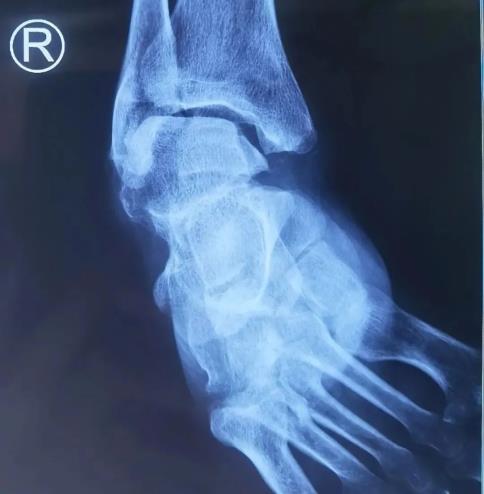

該患者60歲男人,后天原因造成馬蹄內(nèi)翻高弓足,持久右足畸形殘疾,行走非常艱難。入住我院手足內(nèi)科后,我院手足內(nèi)科張曉軍主任、楊金杰醫(yī)師參考患者嚴重畸形,踝足各關(guān)節(jié)畸形高難,傳統(tǒng)手術(shù)矯正危害較大,參考運用3D打印技巧引導手術(shù),提升手術(shù)精確性。

術(shù)前通過ct薄層掃描、計算機建模,再用3D打印體制作模型、術(shù)前丈量計劃制訂手術(shù)計劃、術(shù)中準確截骨、引導手術(shù)。以免手術(shù)醫(yī)師客觀偏差,減小術(shù)中透視損害,使患足術(shù)后到達優(yōu)良手術(shù)成效。